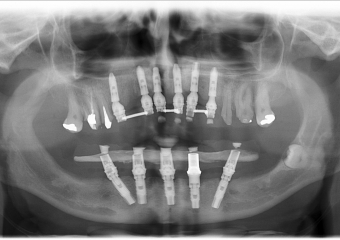

Raio - x Próteses Definitivas em Outubro de 2016  - Clínica Cliniface

Raio - x Próteses Definitivas em Outubro de 2016